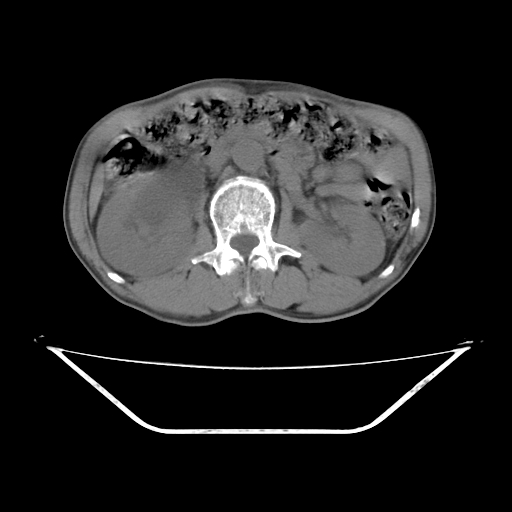

平扫

考虑右肾盂癌,肾动脉受侵,右肾功能减退,右肾盂输尿管积水,管壁增厚,考虑种植转移,应该把下面扫完的

支持右侧肾盂癌伴肾静脉瘤栓形成可能性大,右肾结石.肝右叶后段低密度影,不除外转移.

考虑右肾盂癌,肾动脉受侵,右肾功能减退,右肾盂输尿管积水,管壁增厚,考虑种植转移  支持

右肾盂旁ca并肾静脉瘤栓形成/肾功能降低。

右肾结石。

右肾盂癌,肾动脉受侵,右肾盂输尿管积水,管壁增厚,考虑种植转移

支持 右侧肾盂癌伴肾静脉瘤栓形成可能性大,右肾结石;肝右叶后段低密度影,不除外转移。

1.右侧肾盂癌伴肾盂积水。

2.肾脏功能减退,原因有:(1)肾动脉受侵。(2)肾静脉受侵(3)肾积水,等。本例,肾动脉显影较好,但受压明显;肾静脉无明显显示,受压或静脉癌栓,下腔静脉腔内未见明显充盈缺损。

3.右侧上段输尿管扩张,原因:(1)积水所致;(2)种植。